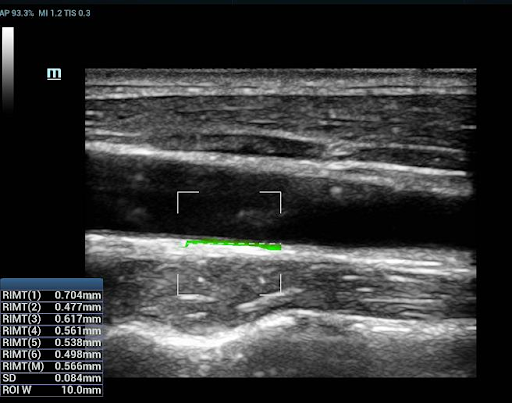

RIMT (RF-Data IMT — измерение толщины комплекса интима-медиа с помощью данных из радиодиапазона)

За счет содержащихся в необработанном акустическом сигнале данных из радиодиапазона (RF-Data), технология RIMT обеспечивает автоматическое измерение толщины КИМ в режиме реального времени с исключительно высокой точностью до 5 мкм, с количественным анализом в пределах 6 сердечных циклов и с меньшей зависимостью от качества изображения – все это значительно повышает точность диагностики.